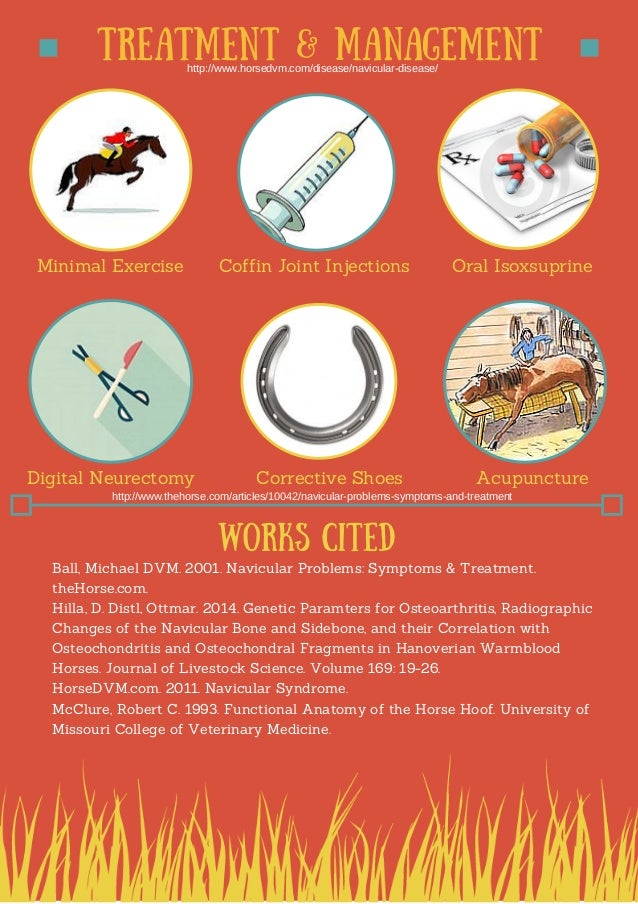

Hooves must be able to expand when they make contact with the ground, plus roll forward efficiently (good “rollover” requires toes to be properly shortened and beveled). The feet must be carefully balanced, with all weight-bearing structures brought into play. A skilled farrier should first remedy any pre-existing problems, including underrun, contracted, or sheared heels mismatched hoof angles or a broken hoof/pastern axis. Shelley PaulsonĬorrect trimming/shoeing should be the basis of all heel-pain treatment, with any medicinal or surgical strategies considered adjuncts. Though navicular syndrome usually can’t be fully cured, proper management and treatment can reduce stress, inflammation, and pain in the affected areas, and some horses may even remain ridable.

The intermittent use of NSAIDs (such as bute) may also be a part of the plan. In addition, depending on the source of your horse’s pain, your vet may propose medical therapies applied systemically or injected into the coffin joint or navicular bursa to reduce inflammation or preserve bone (at right). If your horse does develop heel pain, your vet is likely to recommend therapeutic trimming and/or shoeing (see below). These include correct and regular hoof care, proper nutrition (that prevents obesity), regular exercise plus turnout, and decent footing. To lower the risk that your horse will ever develop navicular syndrome, provide all the horsekeeping standards that are basic to excellent care. MRI and other advanced imaging techniques may be needed the more precise the diagnosis of the cause, the more precise and effective the treatment. Your vet will determine whether your horse has navicular syndrome, then try to pinpoint which disease process is at work. Watch for these symptoms and consult with your veterinarian if any appear: increased stumbling a shortened, choppy stride standing with a front foot pointed front-end tenderness on hard ground or when moving in a circle. Horses with large, heavy bodies and small hooves are at even greater risk. Heel pain can occur to any horse, but the risk is higher for Quarter Horses, Thoroughbreds, and warmbloods, especially those over the age of 7. Palmar heel pain is an alternate term, referring to the site of the nerve block (at the back and bottom of the front feet) that resolves pain for all these conditions.

Navicular syndrome refers to a variety of conditions that create pain in and around the structures surrounding the navicular bone.